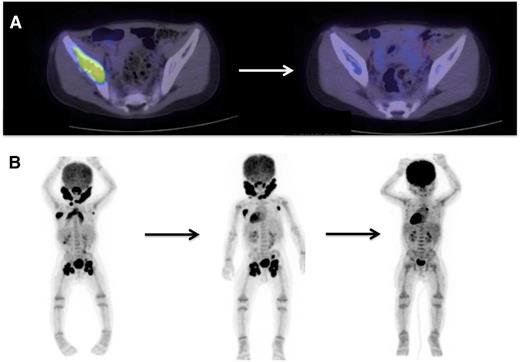

Evaluating disease activity and response to therapy

PET/CT scans are effective to stage disease and to evaluate response to therapy in LCH. Examples of 18-fluoro-deoxyglucose–PET scans with CT identifying response to therapy. (A) A patient with multifocal bone disease with interval improvement of pelvic lesion and decreased PET avidity. (B) A patient with multifocal lymph node disease (cervical, axillary, inguinal) who initially failed to respond to cytarabine therapy, then had significant response to 2 cycles of clofarabine.